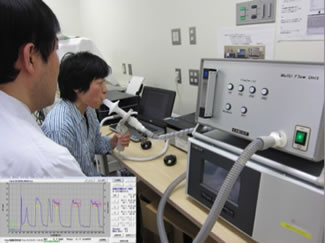

夜間や早朝に悪化し、日中に軽快する咳や痰や喘鳴があるような典型例では診断は容易ですが、咳だけが3週間以上も続く場合は見逃される場合もあり注意が必要です。当科では、患者さんの症状のほかに、呼吸機能検査による可逆性検査や「喀痰中の好酸球の増加」(図3)および好酸球性気道炎症の程度と良い相関関係を示す「呼気中の一酸化窒素(NO)濃度」(図4)の測定などの客観的検査を組み合わせて正確な診断を行っております。

図4. 呼気NO濃度測定検査の実際